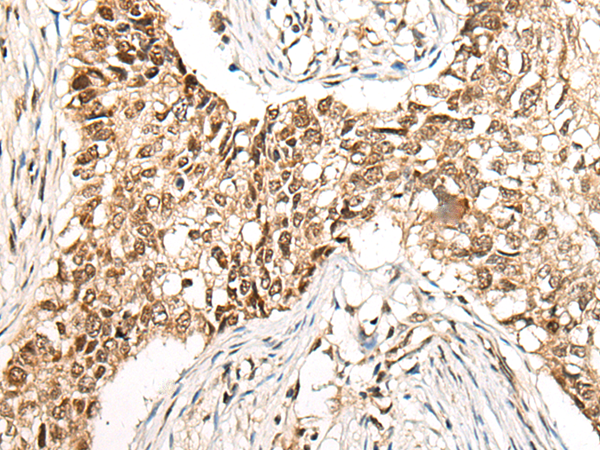

IHC positive control: |

Human lung cancer and human esophagus cancer |

IHC Recommend dilution: |

40-200 |